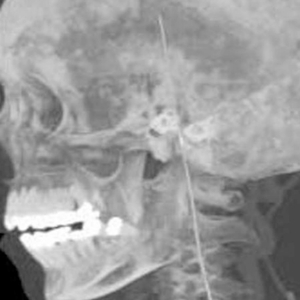

重庆医科大学第一附属医院血管外科曾接诊过一个异物顺着血管到达大脑的病例。该院血管外科在2019年发文称,患者4年前在外院发生导丝血管内丢失,当时手术无法取出。来到该院时,患者已出现脚踝肿胀、头痛症状,检查发现血管内的导丝断成两截,其中一段刺穿血管壁到达大脑。由于手术风险大,患者拒绝手术。

计算机断层扫描三维重建显示,导丝上端已进入大脑位置。图源/期刊Medicine(Baltimore)